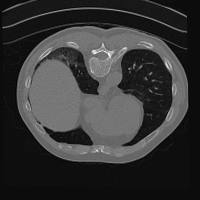

Exp. 3: Adult thorax data: To show the versatility of our approach we also apply it to adult thorax scans. For this experiment no organ specific training is performed but the whole volume is used. We evaluate reconstruction performance similar to Exp. 1 and Ti^^subscript𝑇𝑖\hat{T_{i}} prediction performance when ΩΩ\Omega is projected on an external plane, comparable to X-Ray examination using C-Arms. The latter provides insights about our method’s performance when applied to interventional settings in contrast to motion compensation problems. 60 healthy adult thorax scans were randomly selected, 51 scans used for ΩtrainsubscriptΩ𝑡𝑟𝑎𝑖𝑛\Omega_{train} and nine scans used for ΩvalidationsubscriptΩ𝑣𝑎𝑙𝑖𝑑𝑎𝑡𝑖𝑜𝑛\Omega_{validation}. Each scan is intensity normalised and resampled in a volume of 200×200×200200200200200\times 200\times 200 with spacing 1mm×1mm×1mm1𝑚𝑚1𝑚𝑚1𝑚𝑚1mm\times 1mm\times 1mm. Using the Fibonacci sampling method, 25 sampling plane of size 200×200200200200\times 200, evenly spaced between -50 and +50, were rotated over 500 normals. Training took approximately 20 hours for 60 epochs. Fig. 4c shows an example reconstruction result gaining 28dB PSNR with additional SVR. Ti^^subscript𝑇𝑖\hat{T_{i}} prediction takes approx. 20 ms/slice for this data.

Figure 4: (a): Comparison of a single slice from raw low-dose thorax CT data; (b): reconstruction based on SVRNet Ti^^subscript𝑇𝑖\hat{T_{i}} regression; (c): SVR initialized with SVRNet transformations after four iterations of SVR; (d): PSNR of (b) and (c) compared to (a). (e): shows a projection of an unseen pathological test CT volume as DRR and (e) shows a DRR at the location predicted by our method when presented with the image data in (e).